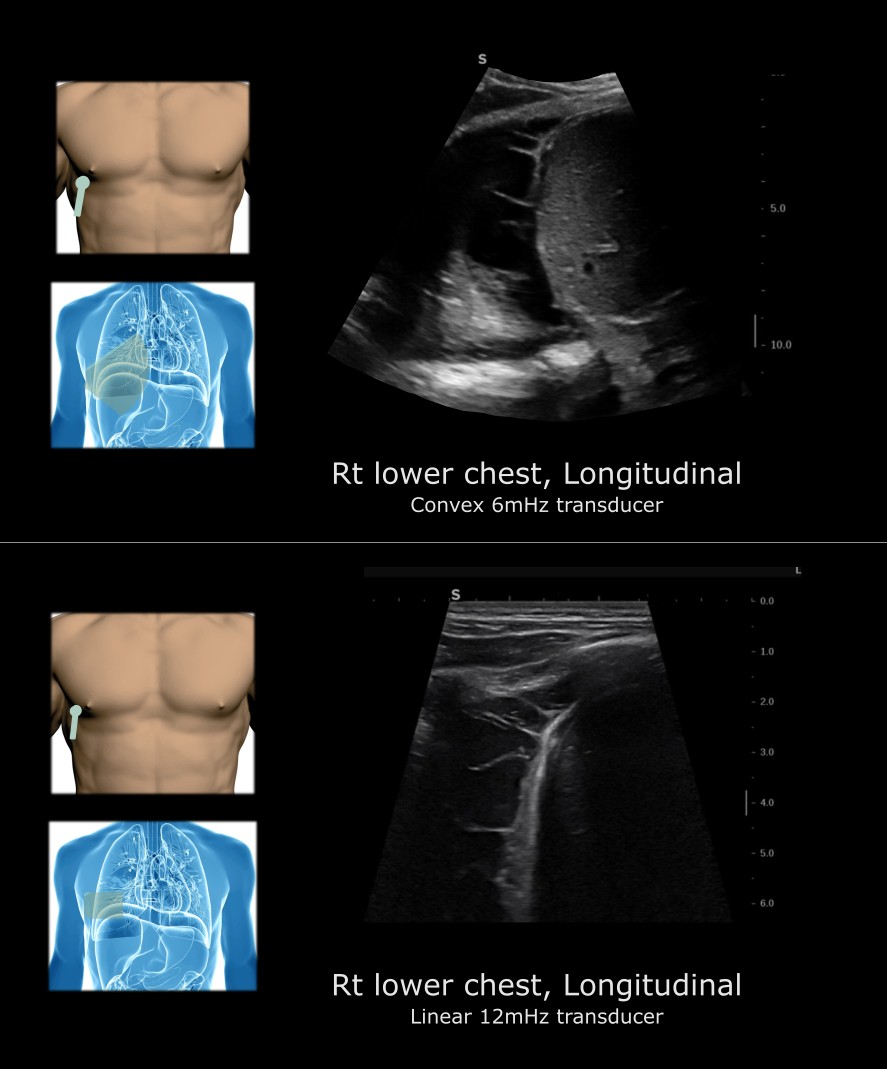

בן 42, קוצר נשימה וחום מזה כשבוע

בבדיקתו: כניסת אוויר מופחתת מימין

מדדים חיוניים: חום מוגבר, טכיקרדי

בבדיקות מעבדה: מדדי דלקת מוגברים

אמפיאמה

* התוכן העכור נצפה טוב יותר במתמר ליניארי ברזולוציה גבוהה